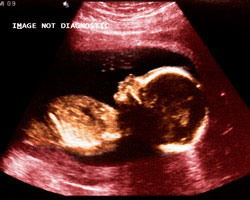

Ecografia das 20 semanas

Já fizeste a consulta ginecológica de controlo? Na 20ª semana de gravidez, aproximadamente, realiza-se a ecografia mais importante da gravidez, a ecografia morfológica.

Nesta ecografia analisam-se os parâmetros mais importantes que avaliam a morfologia do feto, o seu bom estado de saúde e normal desenvolvimento.

Além disso, se se deixa ver, a ecografia morfológica pode dizer-te o sexo do teu futuro bebé! O scanner de anomalias ou anatómico, que observa detalhadamente como se desenvolveram os principais órgãos e sistemas do bebé – cérebro, coluna, lábio superior, coração, estômago e diafragma; rins e bexigam parede abdominal; membros do bebé e cordão umbilical, além de analisar a placenta e o volume do líquido amniótico.

A placenta será examinada para se assegurar que é normal e que não bloqueia a via de saída do bebé, enquanto o líquido amniótico se analisa para comprovar que não há nem em falta nem em demasia.